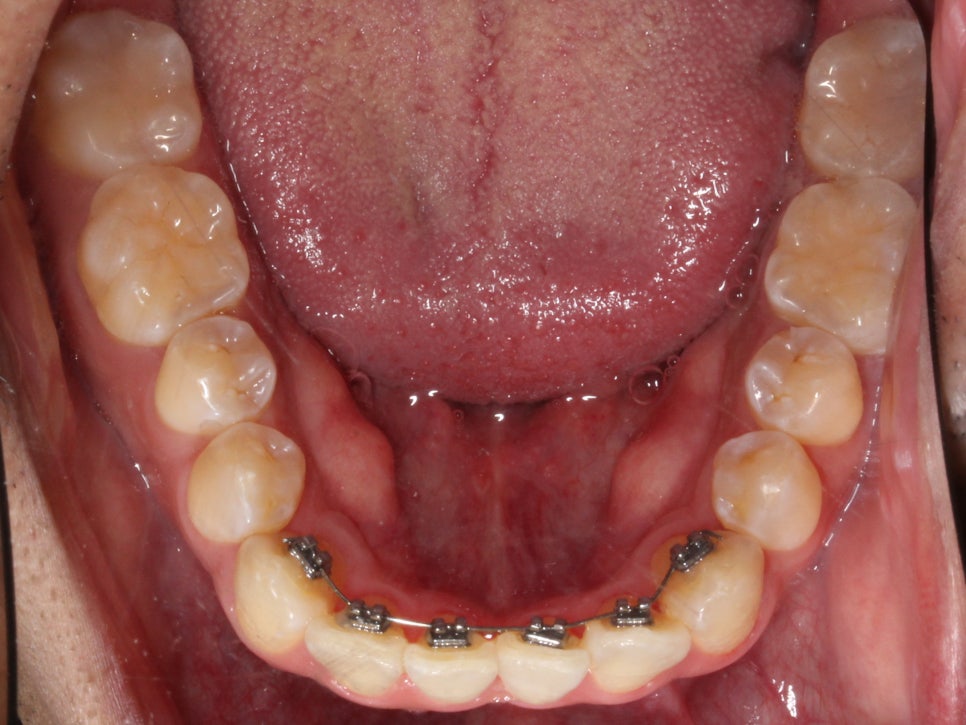

아래 앞니도 공간이 부족해서

약간 삐뚤빼뚤한 모습이 나타나지만

충분히 비발치 부분교정으로

펼칠 수 있는 케이스라 판단했습니다.

아래 치아는 배열될 공간을 만들기 위해

치간 삭제를 동반하여 치료하고 있었고

치간 삭제를 하면서 아래 치아 각도가

조금 더 개선이 되었습니다.

느껴지실까요..?^^